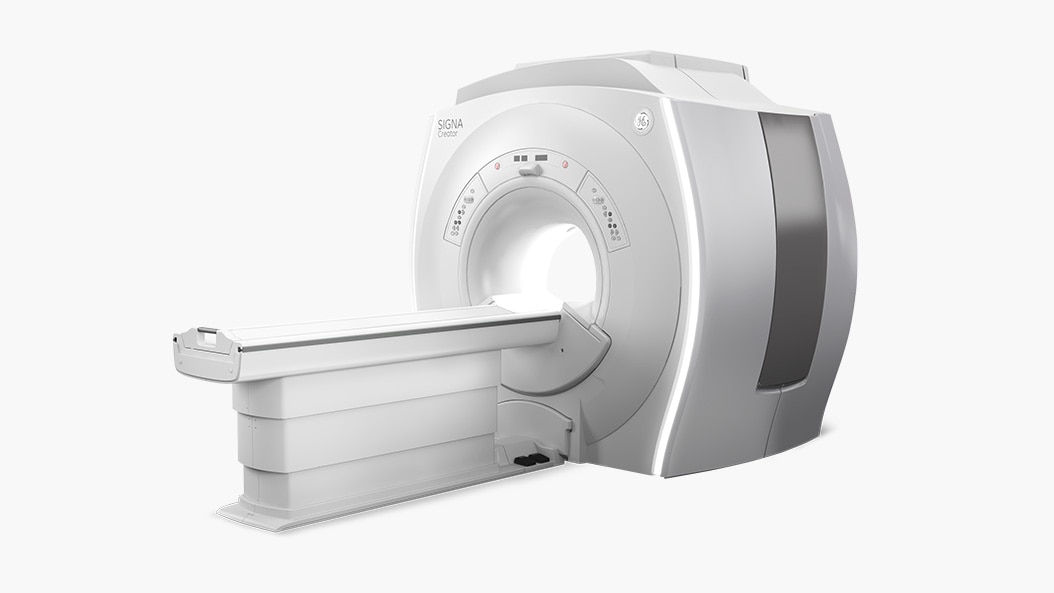

GoldSeal offers affordable high-performance MR systems to help you make accurate diagnoses. The combination of clinical applications and technology improve imaging, while helping you manage data productively. GoldSeal refurbished MR systems help put leading-edge imaging capabilities within your budget.